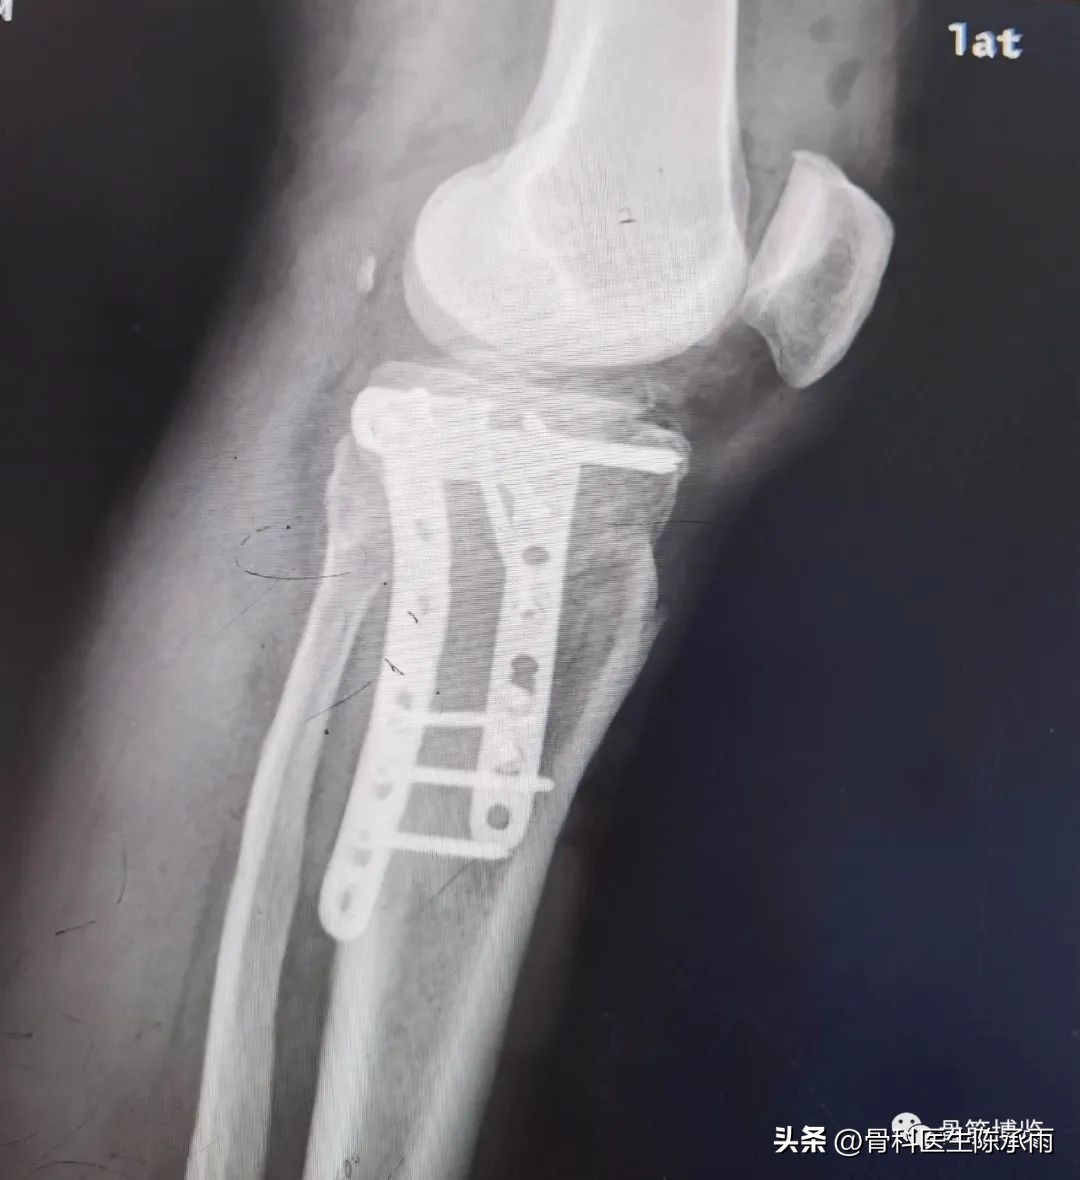

1例

2例

3例

4例

5例

6例

7例